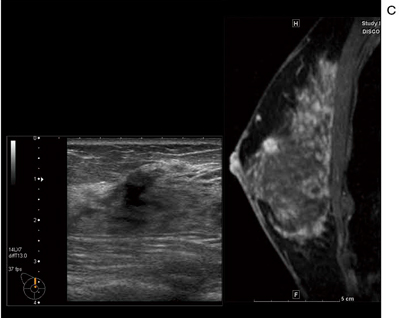

■症例1:40歳代後半,女性。両側乳房腫瘤を自覚,近医で良性と診断。超音波フォロー中に新規病変を指摘されて当院へ紹介。

c:造影MRI矢状断像,Bモード画像,病理像